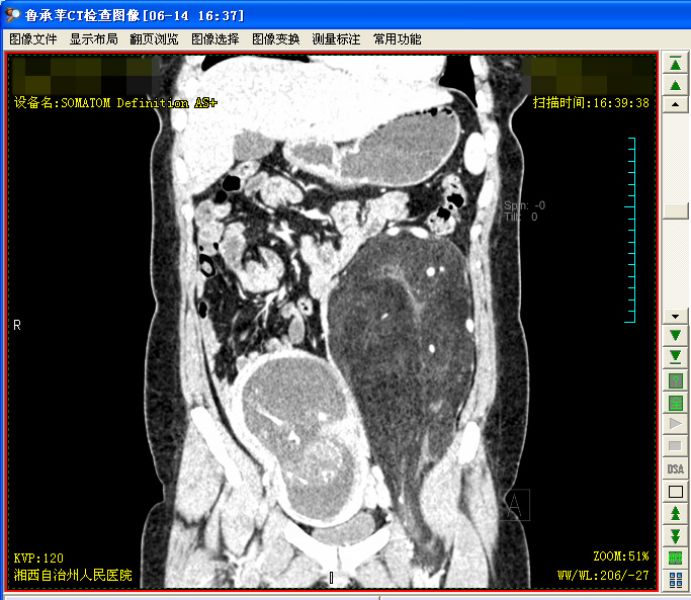

术前腹部增强CT照片

杨闻晓主任和李玉坤主任立即为患者安排了MRI等多项术前检查,同时组织手术室、麻醉科、超声科、产科、介入科等科室进行多学科联合讨论(MDT),多位专家认为:患者为妊娠18周的孕妇,若行手术则术前需要先终止妊娠才能暴露手术视野,同时患者的腹膜后肿块巨大,且与闭孔、髂总血管、股动静脉及腹膜后的神经关系紧密,手术切除难度极大。然而患者及家属的手术意愿十分强烈,肚子里的巨大肿物让鲁女士及家人觉得像一颗随时可能爆炸的“定时炸弹”,最终决定终止妊娠行肿瘤切除手术。

术中发现肿块位于左中下腹腹膜后,质地较软,呈脂肪样改变,肿块推挤降结肠及乙状结肠向右移位,网膜粘连于左结肠旁沟,切开肿块表面覆膜后腹膜,见肿块有完整包膜,肿块表面覆盖腰部神经分支,部分神经分支从肿瘤内部通过,沿肿块表面分离,见输尿管、生殖血管被肿瘤推向内侧,髂动静脉自肿瘤内通过,肿瘤的滋养血管来自左髂、股动静脉。术中先离断肿瘤的滋养血管,并将肿瘤自髂血管剥离,手术历时3个小时完成,切除肿瘤重达8kg。术后病理检查提示:非典型性脂肪瘤性肿瘤/高分化脂肪肉瘤。